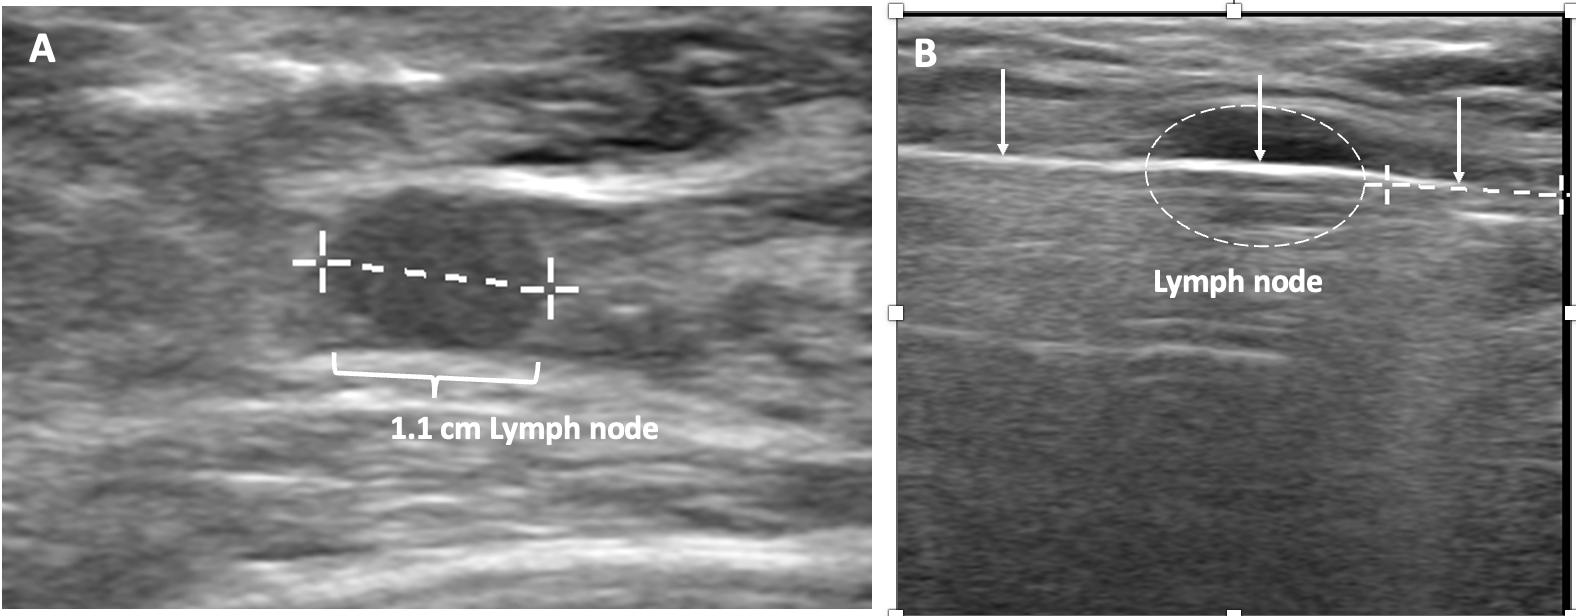

Ultrasound of the axilla. Axillary ultrasound permits detection of abnormal appearing lymph nodes that might not be detected on physical examination, mammography, or breast MRI. Axillary ultrasound is the most sensitive imaging study for detection of subtle changes in the shape or thickness of a lymph node cortex that might indicate the presence of lymph node metastasis (Image 3). Detection of suspicious lymph nodes determines clinical cancer stage and requires a specific plan to manage the possibility of lymph node metastasis.

Image 3. Hash marks outline abnormal appearing axillary lymph node measuring 1.5 cm in maximal diameter. Paired “+” marks indicate the span of a 0.4 cm area of focal cortical thickening that is suspicious for a metastatic deposit within the lymph node.